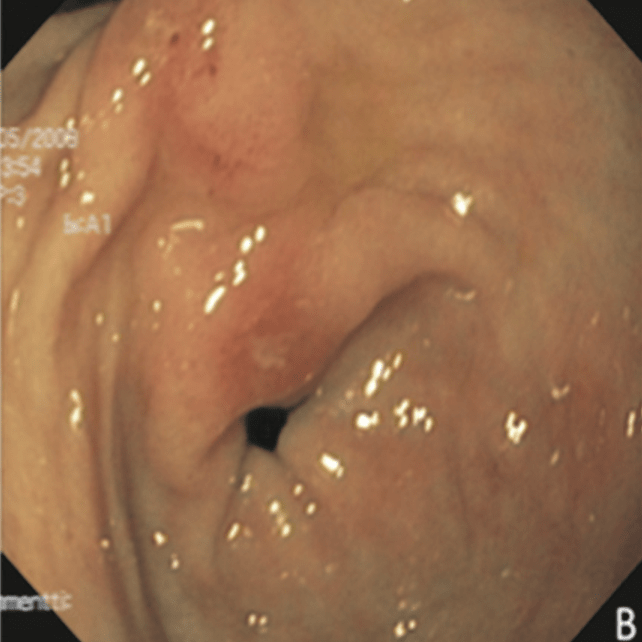

#EndoQuiz: Какой тип по Toljamo?

#EndoQuiz: Правильный ответ - Полная эрозия (I тип)